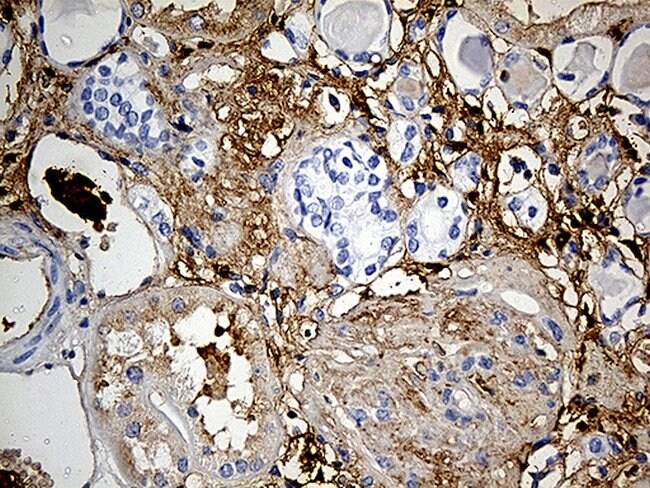

PLG Monoclonal Antibody (OTI4F5), TrueMAB™, OriGene

Plasmin (PLG, Plasminogen) dissolves the fibrin of blood clots and acts as a proteolytic factor in a variety of other processes including embryonic development, tissue remodeling, tumor invasion, and inflammation. In ovulation, weakens the walls of the Graafian follicle. It activates the urokinase-type plasminogen activator, collagenases and several complement zymogens, such as C1 and C5. Cleavage of fibronectin and laminin leads to cell detachment and apoptosis. Also cleaves fibrin, thrombospondin and von Willebrand factor. Its role in tissue remodeling and tumor invasion may be modulated by CSPG4. Plasmin binds to cells.

Immunohistochemistry (Paraffin)